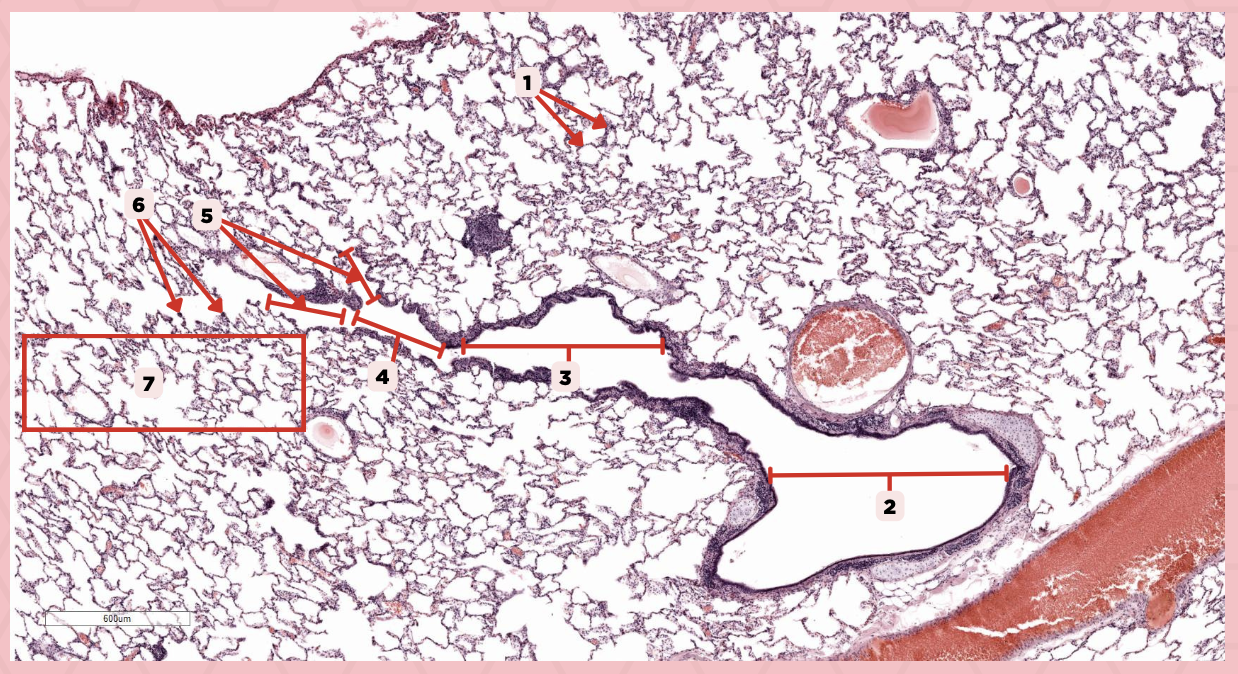

Lumens and Interalveolar septa

Name the irregular spaces and the fine threads of tissue that separate them.

Visceral pleura

Identify the structure labeled as 1.

Alveoli

Identify the structure labeled as 2.

Bigger and smaller intrapulmonary bronchi

What are the two types of intrapulmonary bronchi?

Pseudostratified epithelium (bigger bronchioles), Simple columnar or cuboidal (smaller)

What are the types of epithelium in No. 3?

Interalveolar septa

Identify the structure labeled as 1.

Intrapulmonary bronchi

Identify the structure labeled as 2.

Bronchiole

Identify the structure labeled as 3.

Terminal bronchiole

Identify the structure labeled as 4.

Respiratory bronchiole

Identify the structure labeled as 5.

Alveolar ducts

Identify the structure labeled as 6.

Alveolar sacs

Identify the structure labeled as 7.